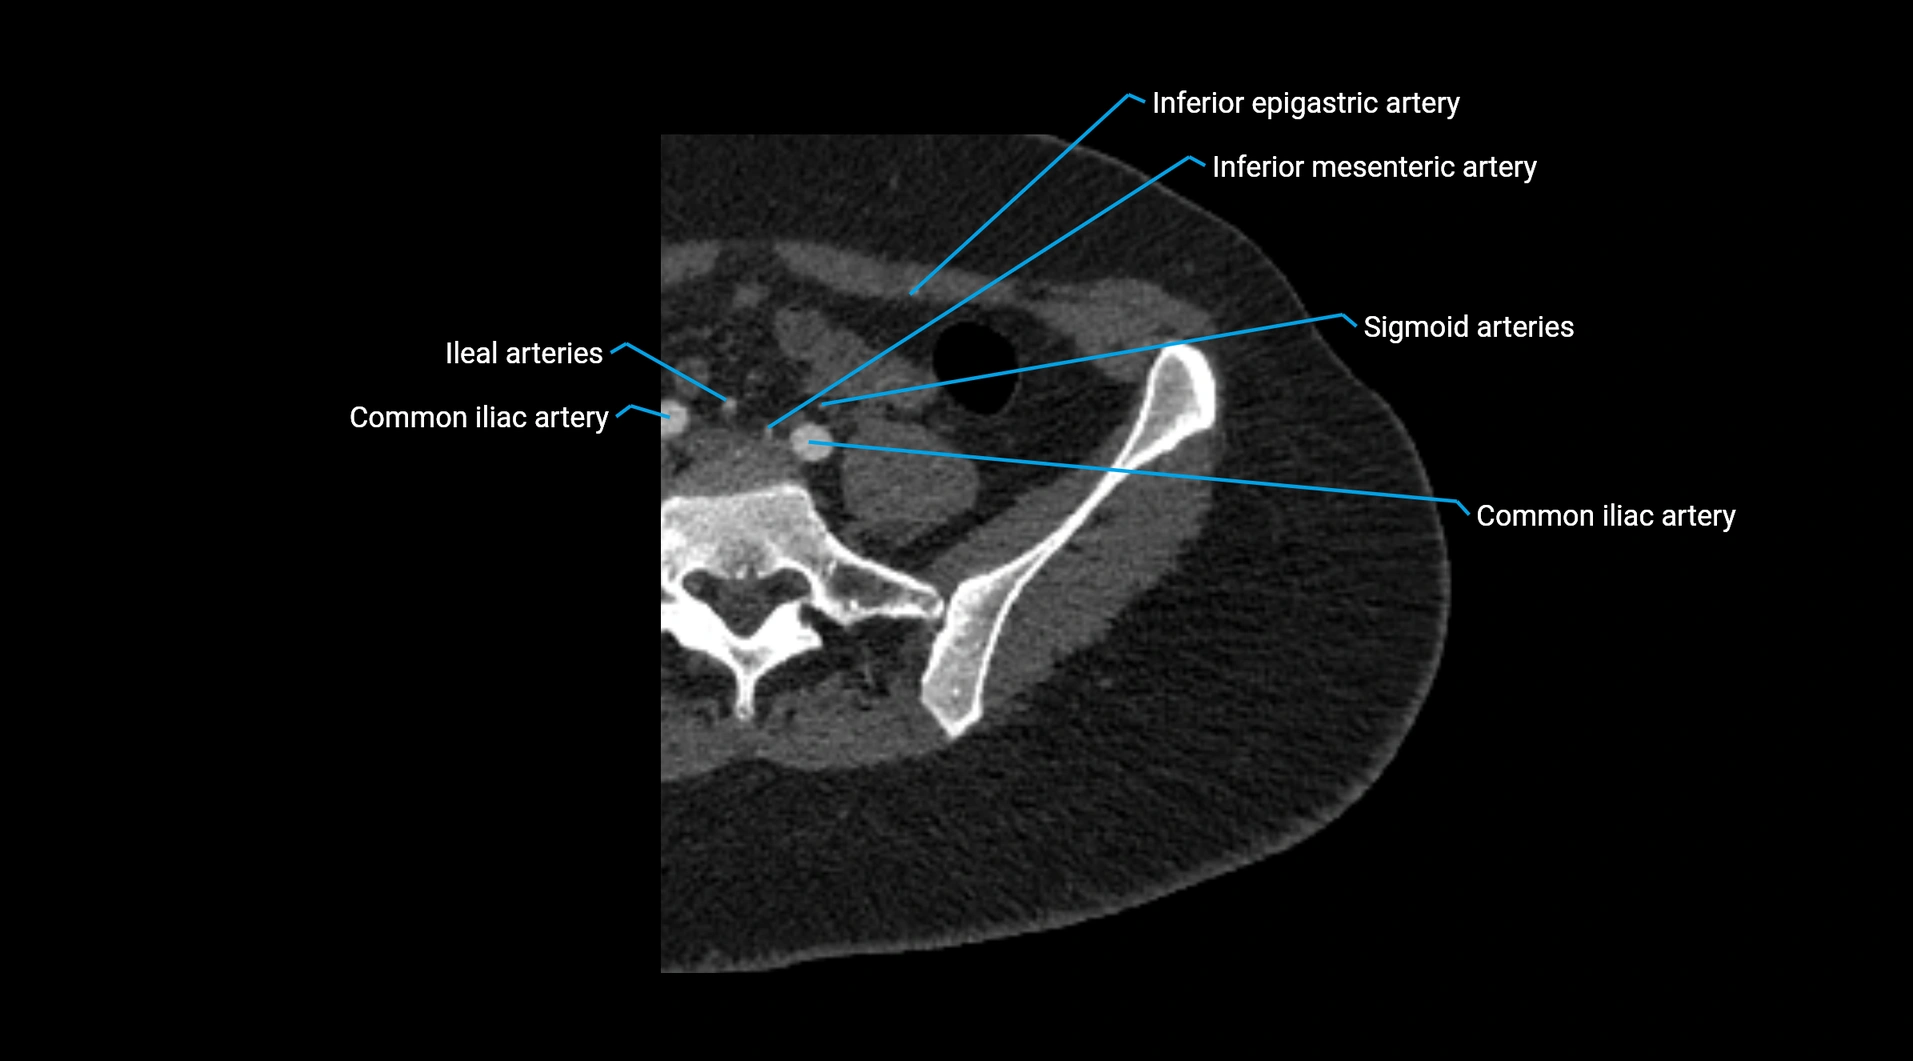

CT Appearance

Non-contrast CT:

• Appears as a tubular soft tissue structure anterior to vertebral bodies

• Calcified atherosclerotic plaques appear as hyperdense foci along the wall

• Useful for screening abdominal aortic aneurysm (AAA) size and mural calcification

Contrast-enhanced CT (CTA):

• Gold standard for abdominal aortic imaging

• Provides excellent detail of lumen, wall, aneurysm, thrombus, and branch vessels

• Multiplanar and 3D reconstructions help in aneurysm measurement, stent graft planning, and dissection evaluation

• Detects acute rupture, traumatic injury, or occlusion with high sensitivity

CT images

image